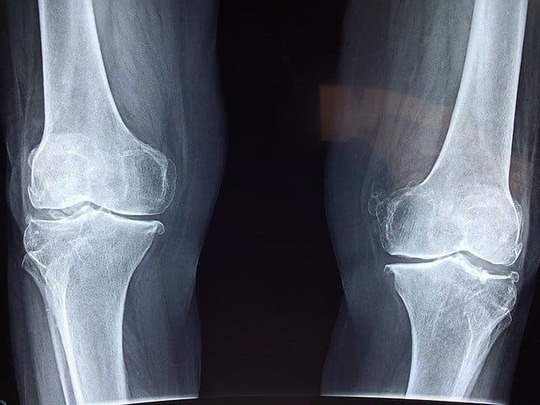

半月板損傷は、膝の曲げ伸ばしの時の痛みやひっかかりを感じる

半月板損傷が起きると、膝を曲げたり伸ばしたりする時の痛みやひっかかりを感じます。半月は膝関節のクッションと関節を安定させるための役割をしています。そのため、損傷すると痛みや引っ掛かりを感じるようになるのです。

半月板損傷の主な症状は、痛みや腫れ、引っかかりなど

半月板損傷の主な症状は、痛みや腫れ、ひっかかりなどです。運動をしたときや膝を曲げたり伸ばしたりしたときにひっかかりを感じます。